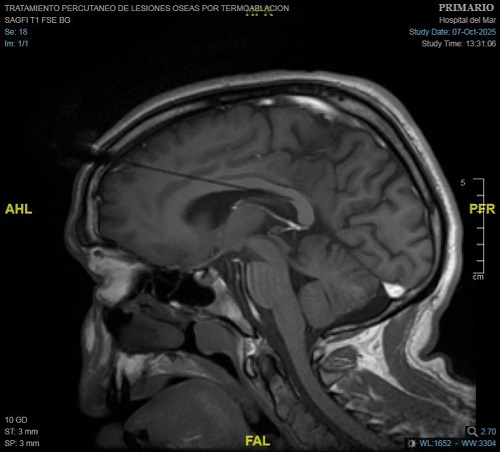

En el primer cas tractat a l'Hospital del Mar, el passat 7 d'octubre, l'equip liderat pel Dr. Carlo Marras, cap del Servei de Neurocirurgia, juntament amb la Dra. Nazaret Infante, metgessa adjunta del mateix servei, van tractar un pacient amb un tipus d'epilèpsia resistent al tractament farmacològic i que no era tributari d'una cirurgia curativa. Després d'un procés de planificació amb imatges 3D junt amb l'equip de la Unitat d'Epilèpsia, encapçalat pel Dr. Rodrigo Rocamora, es va seleccionar l'àrea del cos callós del cervell a tractar per a interrompre la comunicació entre els dos hemisferis cerebrals.

Per fer-ho, amb l'ajuda d'un sistema robòtic, se situen de dues a tres sondes làser a través d'accessos mil·limètrics al crani que serviran, amb monitoratge constant d'imatges de ressonància magnètica, per a fer la intervenció i obtenir el resultat esperat. Gràcies a les altes temperatures que assoleix el làser, s'actua sobre la zona concreta del cos callós seleccionada sense afectar les zones del cervell properes. Així s'assoleix "una lesió molt localitzada", explica el Dr. Carlo Marras. En tot moment es controla la temperatura del làser per a evitar afectar altres zones del cervell.